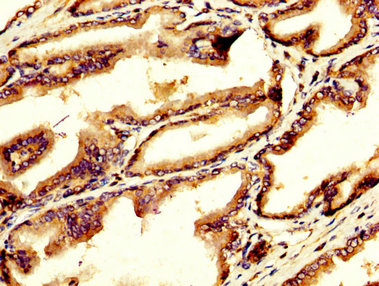

IHC image of CSB-PA009343LA01HU diluted at 1:200 and staining in paraffin-embedded human testis tissue performed on a Leica BondTM system. After dewaxing and hydration, antigen retrieval was mediated by high pressure in a citrate buffer (pH 6.0). Section was blocked with 10% normal goat serum 30min at RT. Then primary antibody (1% BSA) was incubated at 4°C overnight. The primary is detected by a biotinylated secondary antibody and visualized using an HRP conjugated SP system.